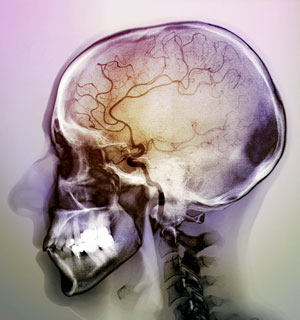

Figure 1: Colored angiogram of the brain of a patient after a stroke. A huge international study has identified 32 genetic factors that increase the risk of stroke. © 2018 ZEPHYR/SCIENCE PHOTO LIBRARY